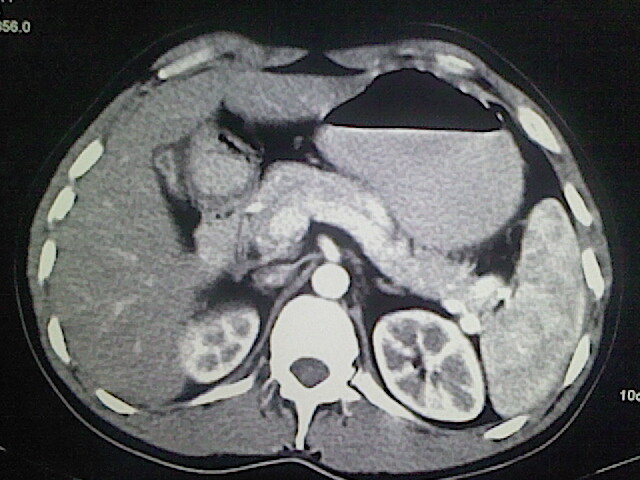

以下是引用卜一在2009-3-14 9:49:00的发言:[br]胆囊萎缩,胆囊壁不规则增厚,内部结构模糊,增强明显强化。另:肝左叶外侧段肝囊肿。支持:慢性胆囊炎!高度可疑:胆囊癌!

以下是引用余辉在2009-3-14 8:48:00的发言:[br]1)慢性胆囊炎。2)肝左叶外侧段肝囊肿。3)脂肪肝。[br]支持,胆囊萎缩,密度增高,不知b超具体有何提示,钙胆汁?结石?

以下是引用jiangjing在2009-3-14 10:18:00的发言:[br]1)慢性胆囊炎。2)肝左叶外侧段肝囊肿。3)脂肪肝。4.】建议行肝功能检查